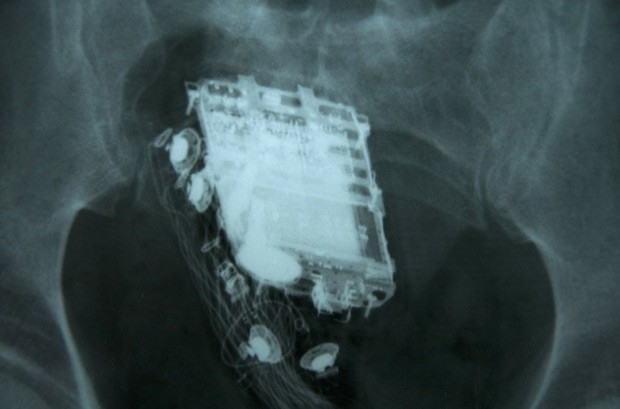

Raio-X mostra o telefone celular no reto de prisioneiro de 58 anos em Colombo, no Sri Lanka (Foto: AFP)